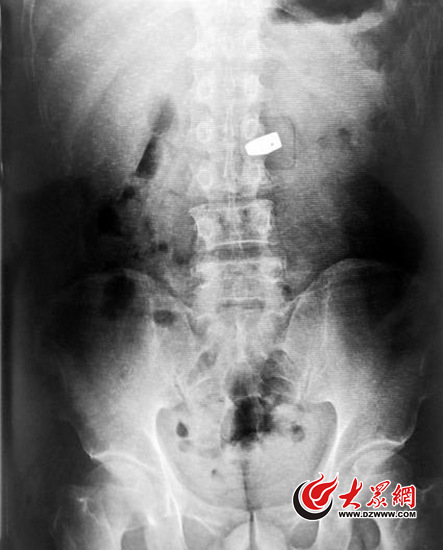

媒體配發(fā)的此圖的“主人”實(shí)為杭州臨平一名中年男子。2010年,該男子在臨平一家銀樓吞下一枚鉆石戒指,這張X光照片是警方調(diào)查時(shí)將他送到醫(yī)院拍下的。

2010年,杭州媒體報(bào)道,一名男子在杭州臨平一家銀樓吞下一枚鉆戒。

有醫(yī)生網(wǎng)友指出,從X光照片中恥骨的角度來看,就可以確定這張X光照片是一個(gè)男性的。

第三張X光照片,它的“主人”是杭州臨平一名中年男子。2010年,該男子在臨平一家銀樓吞下一枚鉆石戒指,這張X光照片是警方調(diào)查時(shí)將他送到醫(yī)院拍下的。

有醫(yī)生網(wǎng)友指出,從X光照片中恥骨的角度來看,就可以確定這張X光照片是一個(gè)男性的。該網(wǎng)友用示意圖說明,男性恥骨下角約為70°至75°,女性的則為90°至100°,差別很大。